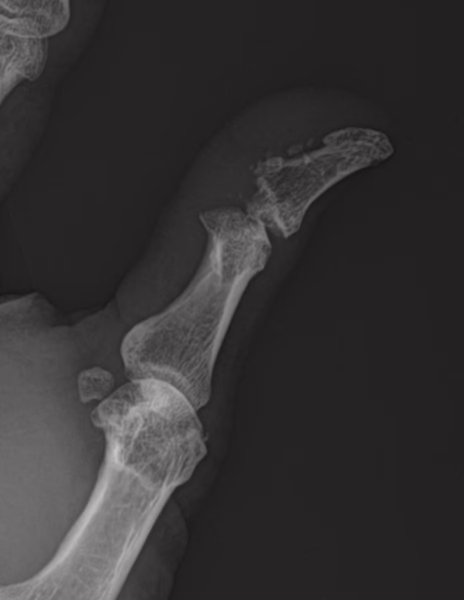

Se realizan radiografías en proyección anteroposterior y oblicua de mano izquierda, donde se observa lo siguiente:

Los tejidos blandos del primer dedo muestran aumento en su volumen. Con presencia de calcificaciones en la superficie palmar de la falange distal del primer dedo.

Se identifica una solución de continuidad cortical en la epífisis distal de la falange proximal del primer dedo.

Estudio radiográfico de mano izquierda con hallazgos que sugieren fractura distal de la falange proximal de del primer dedo.

Edema en los tejidos blandos del primer dedo. Presencia de calcificaciones en la superficie palmar de la falange distal del primer dedo.